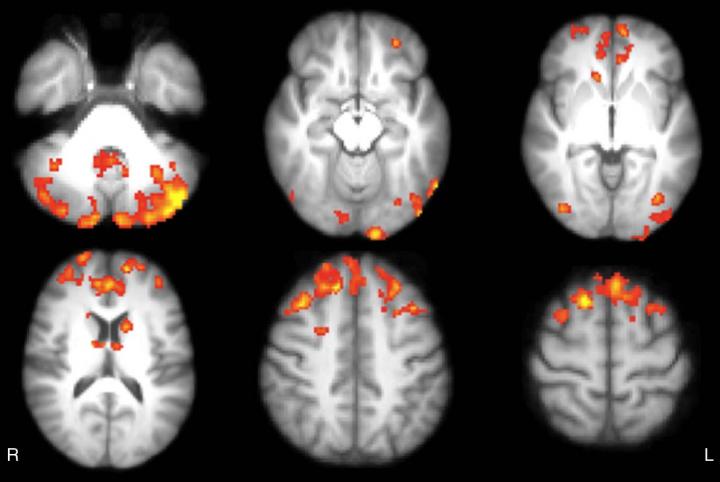

At follow-up, the 12 patients in the video-game group had significant increases in thalamic functional connectivity in brain areas corresponding to the posterior component of the default mode network, which is one of the most important brain networks involved in cognition. The results provide an example of the brain's plasticity, or ability to form new connections throughout life.

The modifications in functional connectivity shown in the video game group after training corresponded to significant improvements in test scores assessing sustained attention and executive function, the higher-level cognitive skills that help organize our lives and regulate our behavior.